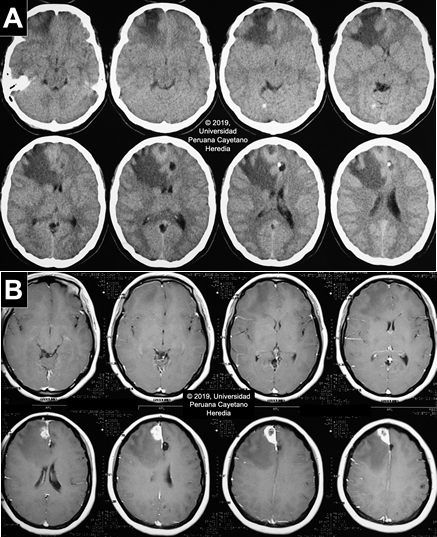

Imaging studies: Normal CXR. Non-contrast head CT scan reveals a hypodense lesion in the right frontal lobe with extensive perilesional edema that produces a midline shift that compresses the right lateral ventricle. No apparent hydrocephalus. Two cystic lesions are present in the left parietal lobe and in the parasagittal frontal lobe. Multiple thick calcifications are found in the parenchyma (Image A). The MRI finds the same parenchymal fluid-filled cystic lesions with a punctiform structure inside. In the contrast T1 view, there is a heterogeneous hyperintense area, with a hypointense center, near the meninges in the right frontal lobe associated with moderate edema, suggestive of a granulomatous process (Image B).

![]() Discussion: Serum Western Blot for Taenia solium was positive (Reactive in 5 bands: 42kd, 35kd, 31kd, 24kd, 14kd). Stool O & P testing was negative. Upper abdominal US was unremarkable. Neurocysticercosis (NCC) is a disease caused by the larval stage of the pork tapeworm Taenia solium and contributes to approximately 30% of the burden of seizures in endemic areas in the developing world (PLoS Negl Trop Dis. 2010 2;4(11):e870), which includes the most Latin American countries, Sub-Saharan Africa, Southeast Asia, China and the Indian subcontinent.(PLoS Negl Trop Dis. 2012 29;6(5):e1500). In the United States, it is estimated that there are 2,361 inpatient cases per year with an economic impact of US $908,238,000 per year and US $50,000 per hospitalization (Emerg Infect Dis. 2015;21(6):969–76; Am J Trop Med Hyg. 2015;92(2):354–9). Humans become infected by accidental ingestion of eggs from feces; the eggs then develop into a larval stage (cysticercus) in several tissues with a marked preference for the CNS and muscles. Infection and development into the adult stage (intestinal tapeworm), occurs when cysts in undercooked pork meat are ingested. The adult tapeworm elongates forming new segments called proglottids, which eventually detach and are shed in stools. These contain thousands of eggs that have the potential to infect new hosts or continue to infect their present host. The spectrum of clinical manifestations is based on the acute or long-term effect of the inflammatory reaction and mass effect. These vary according to the staging and location of the cysts. Parenchymal cysts could present with headaches or seizures, while intraventricular cysts may obstruct CSF flow and cause acute obstructive hydrocephalus (Radiology of Infectious Diseases. 2015 M;1(2):94–102). Active CNS lesions can be identified by CT or MRI; the former excels at identifying calcifications while the latter distinguishes smaller lesions and scolices and provides greater insight for evaluating degenerative changes and edema (Neuroimaging Clin N Am. 2012;22(4):659–76). Neuroimaging findings vary according to the involution of the cysts; our patient presents with lesions on different stages. On CT scan, live vesicular cysts are well-defined, isodense fluid-filled round lesions without surrounding inflammation that does not enhance after contrast administration: scolex may be seen within the cyst as a hyperintense bud, the “hole-with-dot” sign [White arrow in Image C and D]. As the immune system recognizes the cyst, the lesion begins to degenerate into the colloidal stage [Yellow arrows in Image C and D], which presents with poorly-defined borders and extensive perilesional edema seen as a ring-enhancement lesion. No scolices are observed during this stage. The granular stage presents as an entirely collapsed cysts by the host’s immune response. It is also described as small annular or nodular lesions that enhance after contrast administration. The last stage of the lesion, the calcified cysticerci [Image A], is a non-enhancing hyperdense nodule on the CT scan (Radiology of Infectious Diseases. 2015;1(2):94–102; Infect Dis Clin North Am. 2019;33(1):153–68; Neurol Clin. 2018;36(4):851–64). Although most of the images are compatible with NCC, the lesion on the right frontal lobe is atypical and the differential diagnosis is extensive including brain abscesses, tuberculosis, toxoplasmosis, primary brain tumors (meningioma) or metastases. However, due to the presence of other pathognomonic lesions and a positive Western Blot result, we can deduct that this is a cysticercus in a degenerative stage. Anticonvulsant administration is the first step in the management of NCC patients presenting with seizures. Pain management should also be a priority. In the case of raised intracranial pressure options include the use of steroids, acetazolamide, mannitol or surgery, usually shunt placement if there is hydrocephalus (Neurol Clin. 2018;36(4):851–64). Antiparasitic regimens of choice include albendazole alone or combined with praziquantel. Corticosteroids must be given to these patients as there is an initial inflammatory response from the death of the parasites. Additionally, prior to initiation of therapy, ophthalmologic examination should rule out the presence of cysticerci in the eye since degeneration of the cyst can impair vision. The inflammatory response varies between patients and it may be severe when there are multiple or large lesions. This is why starting therapy is not an emergency; each case must be evaluated and individualized accordingly. Our patient was managed with mannitol and acetaminophen to alleviate symptoms while MRI and Western Blot were obtained. Due to the current extensive inflammatory process caused by the lesion’s degeneration, antiparasitic treatment was delayed and the patient was discharged to be closely follow at our outpatient service. The neurologists following her case have requested an imaging follow-up in a month to reassess the appropriate time of starting therapy, which will depend on the decrease of the current inflammatory reaction in the right frontal lobe. Prevention of transmission of eggs between humans includes community awareness programs, good personal hygiene (especially among cooks and servers in the food industry), treatment for tapeworm carriers and administration of anthelmintic chemotherapy in pigs. Our patient was not aware of any household contact with T. solium infection so it’s possible that transmission may have occurred due to her eating habits and the poor hygiene standards of street food vendors. A study in a highly endemic region in Northern Peru tested several strategies for T. solium control that involved human and pig hosts. Results were promising as there was a clear decrease in the number of pigs infected among 107 rural villages (N Engl J Med. 2016;374(24):2335–44). The World Health Organization (WHO) identifies neurocysticercosis as a neglected tropical disease and has prioritized Taenia solium as the focus for new control initiatives. |